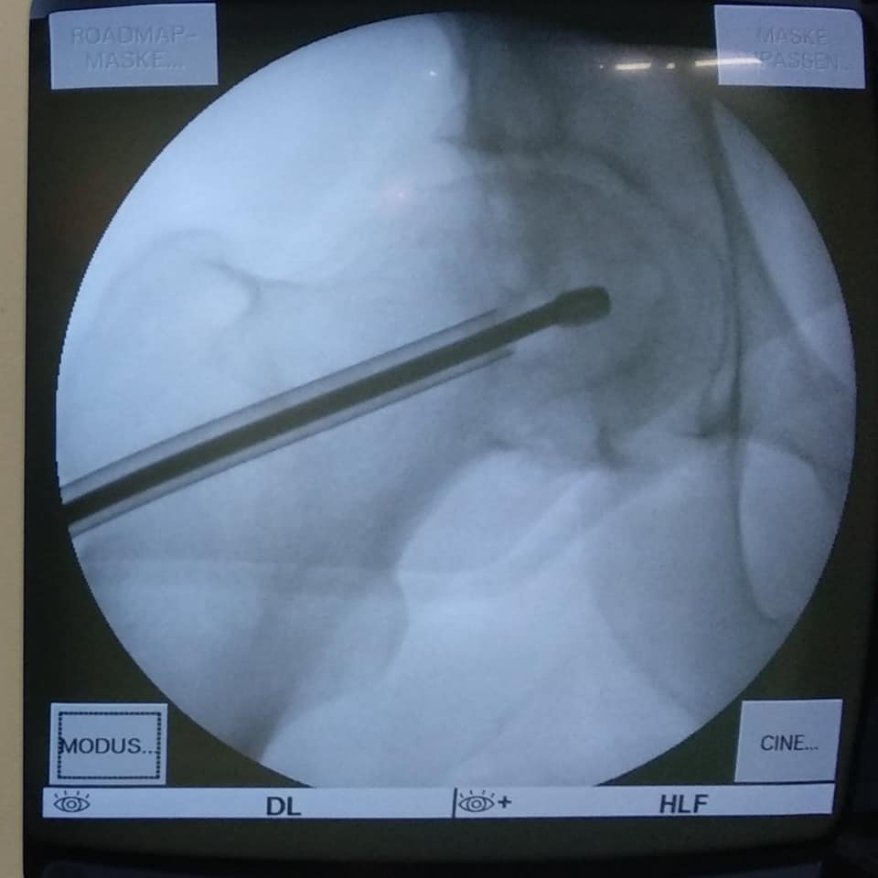

Ця операція полягає у видаленні вмісту кисти, очищенні її стінок та виповнення дефекту кістковим трансплантатом з доступу розміром 3 см.

Перевагами цього методу є – збереження суглоба пацієнта, малоінвазивність та рання мобілізація з максимально швидким поверненням до повноцінного життя.